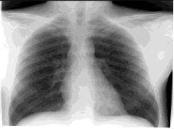

Рентгенологическое исследование органов грудной клетки. Показано при сохранении симптомов острого бронхита более 10 дней (в пределах этого срока при благоприятном течении заболевания должна быть положительная динамика) либо в случае, когда пациент с кашлем последние 2 года не проходил планового флюорографического обследования. При остром бронхите ло кальные изменения легочной ткани (очаги, инфильтраты, фокусы, кольцевидные тени) отсутствуют, иногда наблюдают усиление легочного рисунка.